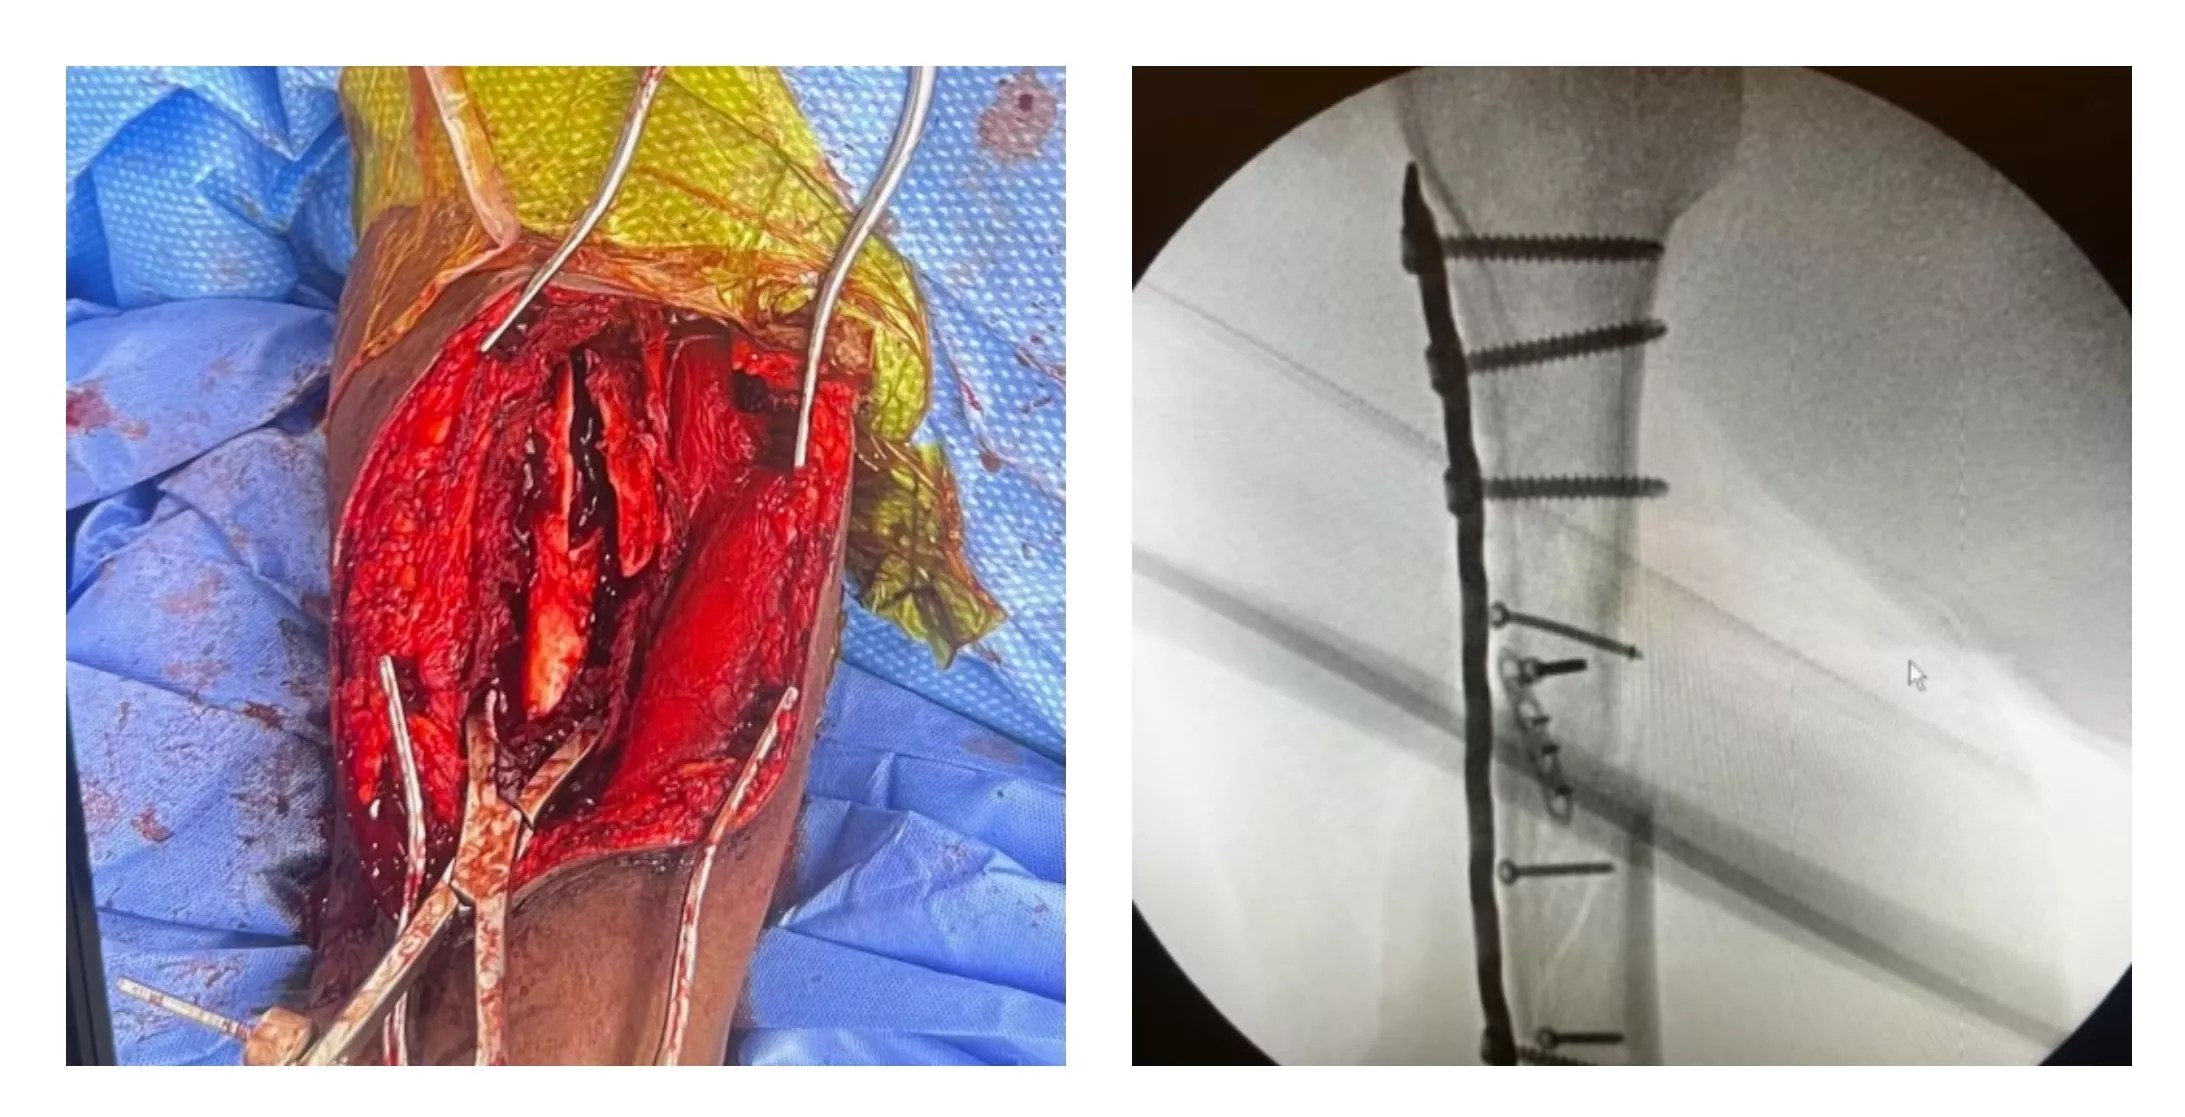

Glover doesn’t go into detail about the injuries sustained by Waddy. But bystander Weldehiwet was shot in the arm amid the chaotic scene, and the bullet did tremendous damage, as seen in the photos below.

A surgical image and an X-ray show the damage inflicted on Yekalo Weldehiwet, an innocent bystander shot by police on July 17.